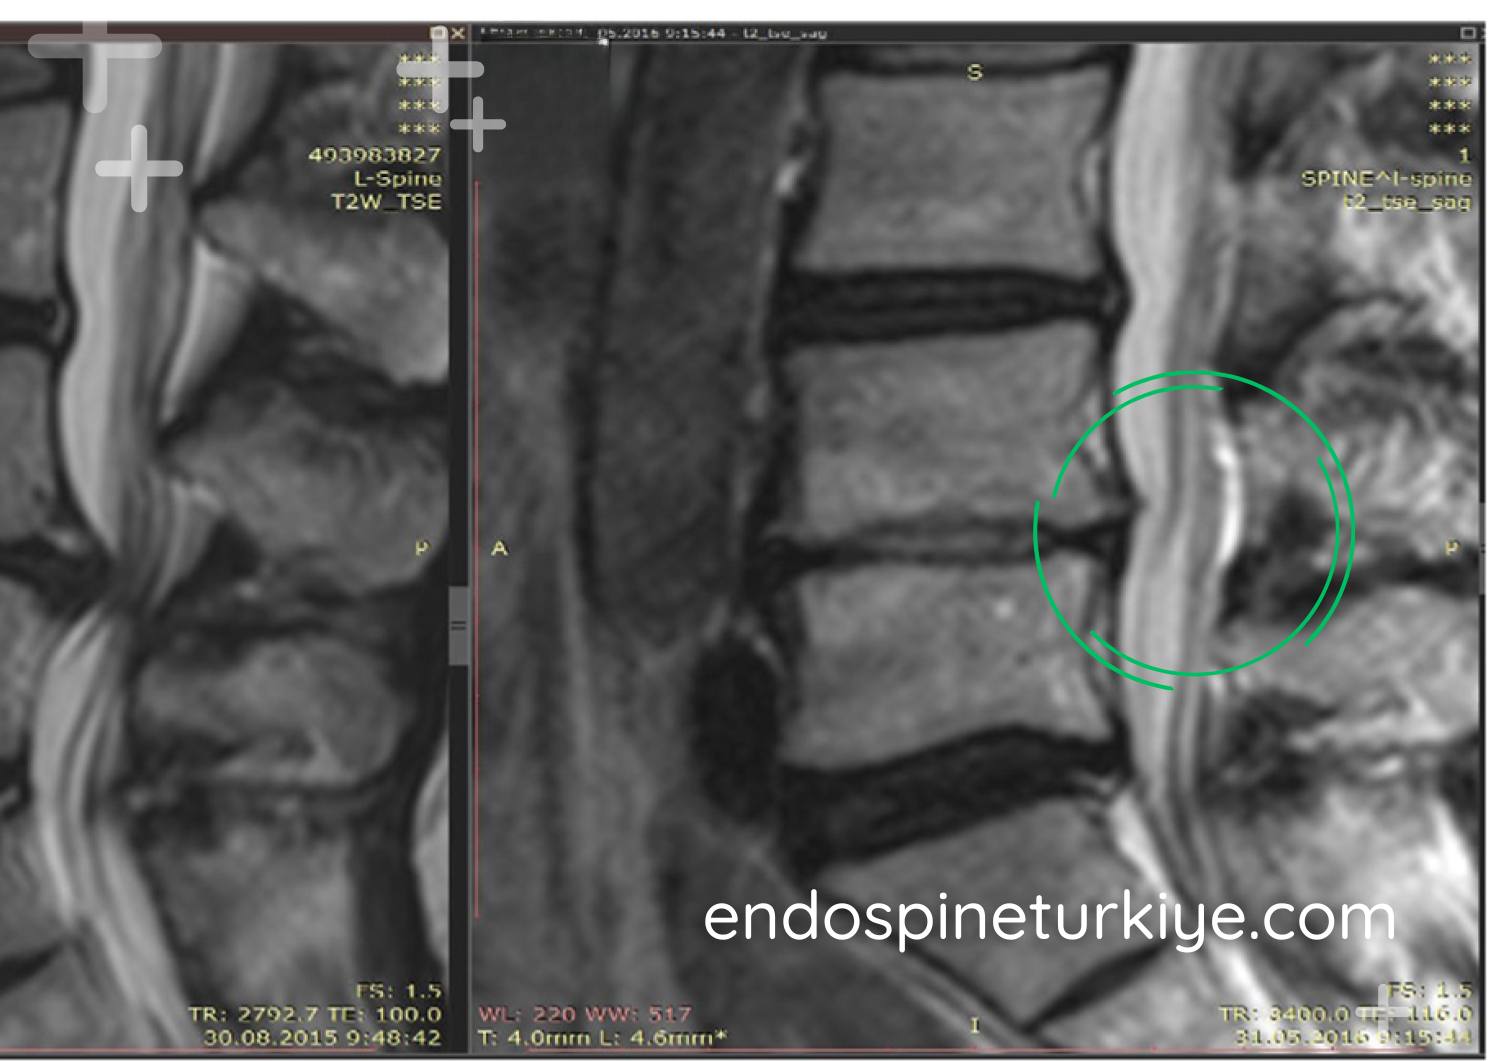

Bel fıtığı tedavi öncesi MR görüntüsü - sinir basısı görülen lomber disk hernisi Tedavi Öncesi

Bel fıtığı tedavi sonrası MR görüntüsü - endoskopik ameliyat ile sinir basısı giderilmiş Tedavi Sonrası

MR görüntülerinde endoskopik bel fıtığı ameliyatı öncesi ve sonrası karşılaştırma